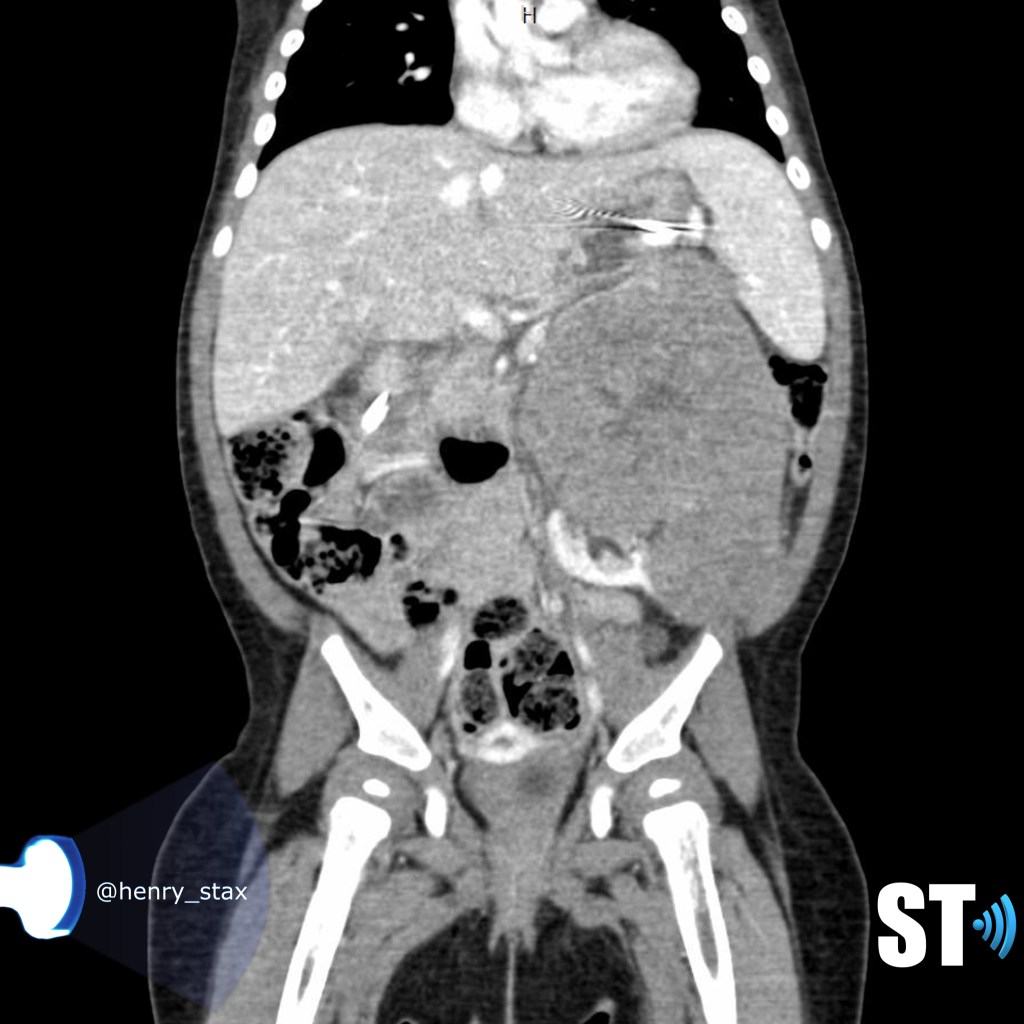

Renal Trauma

Renal trauma accounts for approximately 1-5% of all trauma admissions and as many as 10% of patients who sustain abdominal trauma. Injuries can range from contusions to life threatening injury. The types of trauma include penetrating (gsw, knife), blunt force (mva, sports injury), post procedure etc..

Patients may have abdominal/flank pain on the affected side, hematuria may also be present.